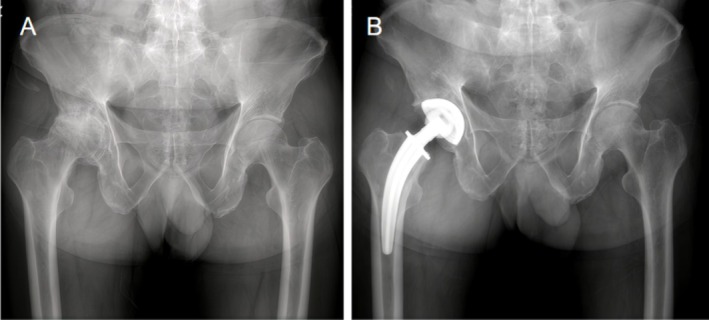

背景:全球全髋关节置换术(THA)的增加导致无水泥股骨干的广泛使用。colum Femoris Preserving (CFP)柄最初被设计为一种骨骺稳定假体,旨在保护近端骨并减少应力屏蔽。然而,长期观察显示意想不到的近端骨吸收和远端硬化,挑战了这种分类。本研究旨在重新评估CFP系统的固定模式和长期并发症,为临床决策提供依据。方法:2006年至2012年,纳入497例患者(705髋)。主要结果包括假体存活、假体周围骨重塑和临床结果,采用Harris髋关节评分(HHS)进行评估。Kaplan-Meier生存分析以假体松动和再手术为终点。影像学资料分析评估假体周围骨重塑。结果:共纳入497例患者(705髋),平均随访10.4年。CFP茎的长期生存率为95.32%,无菌性松动生存率为97.2%,再手术生存率为95.5%。并发症包括2.84%无菌性松动,0.99%感染,0.99%假体周围骨折,0.57%脱位,1.42%异位骨化。CFP假体没有无菌性松动的迹象,显示出远端稳定假体的影像学特征。结论:CFP假体的长期存活率为95.32%。影像学结果表明,CFP假体应被视为远端稳定假体,而不是传统意义上的骨骺稳定假体。

Results: A total of 497 patients (705 hips) with a mean follow-up of 10.4 years were included. The long-term survival rate of the CFP stem was 95.32%, with a 97.2% survival rate for aseptic loosening and 95.5% for reoperation. Complications included 2.84% aseptic loosening, 0.99% infection, 0.99% periprosthetic fractures, 0.57% dislocation, and 1.42% heterotopic ossification. The CFP stem, which has not shown signs of aseptic loosening, exhibits radiographic features characteristic of a distal-stabilized prosthesis.

Conclusion: The long-term survival rate of the CFP prosthesis was 95.32%. Radiographic findings indicate that the CFP prosthesis should be considered a distal-stabilized prosthesis rather than the traditionally regarded epiphyseal-stabilized prosthesis.